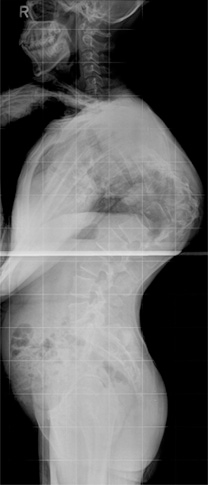

정상적으로 흉추는 기립 측면상에서 20~45도의 후만을 이루고 있습니다. 흉추 후만의 첨부는 제 7 흉추에 위치하며 흉추 후만각은 Cobb 방법상 제 4~12 흉추 사이의 각도를 측정합니다. 일반적인 방사선적 진단 기준으로 Schmorl 결절, 불규칙한 척추 종판, 추간판 간격의 협소를 동반한 적어도 3개 이상의 인접 척추의 5도 이상 설상변형이 제시됩니다. 척추 후만은 경직성으로 신전 시에도 변형이 남아 있으며 신전 시 측면 사진을 이용하여 만곡의 경직도를 가늠할 수 있습니다. 전후방 사진상 다양한 정도의 측만이 환자의 약 1/3에서 동반되어 있으며 척추 전방전위증이 동반된 경우도 있습니다. 동반된 척추 전방전위증은 대부분 협부형으로 대상성 요추 과전만으로 인한 추궁 협부의 긴장으로 설명됩니다. 변형의 유형에 따라 흉추형과 흉요추형으로 나눌 수 있으며 흉추형인 제 1형이 더 흔한 형으로 만곡의 첨부가 제 6~8 흉추 사이에 위치하며 흉추 후만증과 함께 경추와 요추의 과전만을 보이고, 흉요추형인 제 2형은 보다 드물며 만곡의 첨부가 제 10 흉추와 제 1 요추 사이에 위치한 흉요추부나 요추부의 후만증을 보입니다. 흉요추형이 보다 유연한 만곡을 가지며 늑골의 지지가 없으므로 만곡이 진행하는 경향을 보입니다.

주로 축성 골격을 침범하고, 천장관절을 침범하여 천장 관절염을 유발하며 통상 청소년기 후반에 증세의 발현이 시작되는 경우가 흔하고, 40세 이후의 증상 발현은 매우 드뭅니다. 남녀의 성비는 2~3:1의 비율로 남성에서 많습니다. 가장 특징적인 조기 증상은 만성적인 요추부 동통 및 강직이고, 요부 강직은 특히 아침에 가장 심해지고 더운 목욕이나 강한 육체적 운동으로 호전되는 것이 특징적입니다. 통증은 요추부에서 상부 흉추부, 경추부로 이동하며 강직이 수반되고 완전 강직이 된 후에는 통증이 어느 정도 사라지게 됩니다. 질병이 진행될수록 동통으로 인하여 정상적인 자세를 취하기 어려워져 웅크리는 자세로 강직되며 요추부는 전만곡이 소실되고 흉추부는 후만이 증가되며 경추부도 전만이 소실되어 심한 경우에는 턱과 가슴이 붙을 정도의 심한 변형이 발생되고 따라서 전방 주시가 불가능하여 외출 시 사고의 위험성이 많고 불량한 외적인 자세로 인하여 사회적인 생활에 상당한 어려움을 초래하게 됩니다. 초기 방사선 소견으로는 천장 관절면의 불분명과 전방 척추체의 사각화가 관찰되며 질병이 진행됨에 따라 천장 관절의 골성 유합, 전종인대 및 후종인대의 골화가 이루어지고 방사선 사진 상 마치 대나무 같다고 하여 이를 죽상 척추(bamboo spine)라고 칭하기도 합니다.